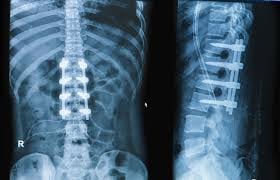

Transforaminal lumbar interbody fusion (TLIF) is a spinal fusion surgery used to stabilize the lower (lumbar) spine. It is primarily advised for patients suffering from chronic back pain, leg pain (sciatica), or spinal instability due to conditions such as degenerative disc disease, spondylolisthesis, spinal stenosis, or recurrent disc herniation.

In TLIF, the surgeon approaches the spine through the side of the vertebra (transforaminal route), removes the damaged intervertebral disc, and places a bone graft or cage between the two vertebrae. Over time, the vertebrae fuse into a single, solid bone. The fusion eliminates painful motion at the joint and restores stability to the spine.

- Placing Screws and Rods: To stabilize the spine, the surgeon inserts pedicle screws and rods into the vertebrae above and below the disc space. These implants hold the bones in place while fusion occurs.